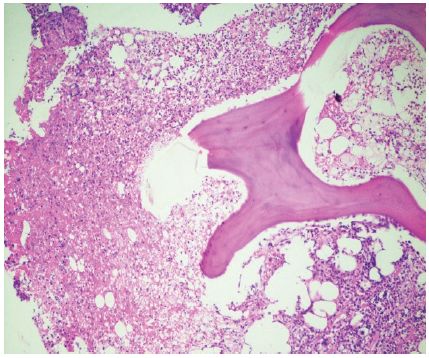

Histopathology revealed necrotizing granulomatous osteomyelitis consistent with a mycobacterial etiology, and Ziehl–Neelsen staining demonstrated occasional acid-fast bacilli (Figs. 5 and 6). Based on these findings, a diagnosis of tubercular osteomyelitis of the pubic symphysis with secondary MRSA infection was established.

Figure 5: Photomicrograph showing bony trabeculae on the right and necrotic material with inflammatory infiltrate on the left side (Hematoxylin and Eosin, ×100).